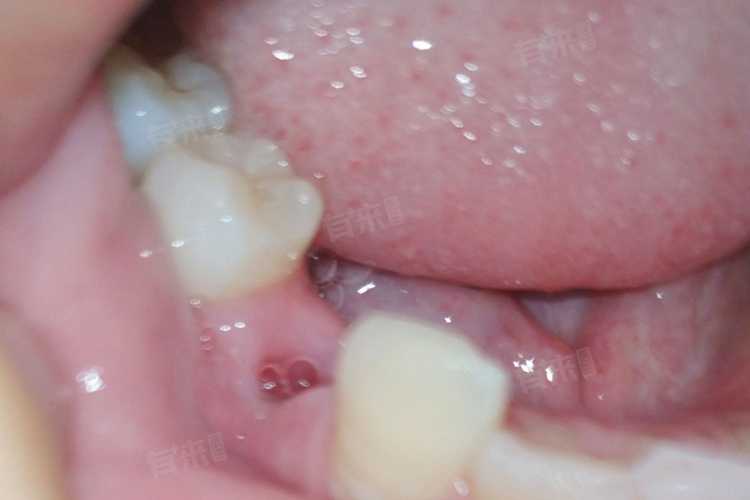

拔牙后,口腔内存在创口,因此在饮食选择上,应以温和、易咀嚼、营养丰富为原则。可以从拔牙后当天、拔牙后1-2天、拔牙后3-7天等来决定进食的食物种类。

3、拔牙后3-7天:创口进一步愈合,此时可适当增加食物种类,但仍要避免过硬、过黏的食物。可选择一些软质的固体食物,如豆腐,富含蛋白质,质地软嫩,烹饪方式多样,可采用清蒸、炖煮等清淡的做法。香蕉富含钾等矿物质,且质地柔软,易于咀嚼,有助于补充身体所需营养。鱼肉富含优质蛋白质和不饱和脂肪酸,选择刺少的鱼类,如鲈鱼、鳕鱼等,烹饪成鱼肉泥或清蒸后小心食用,既能保证营养摄入,又不会因鱼刺问题损伤创口。这些食物营养丰富,能满足身体在恢复过程中的营养需求,促进拔牙创口的愈合。

拔牙7天以后,基本可以恢复正常饮食,但还是需要注意尽量避免辛辣、刺激性的食物。并且注意维护口腔卫生,按时刷牙、漱口,避免感染。